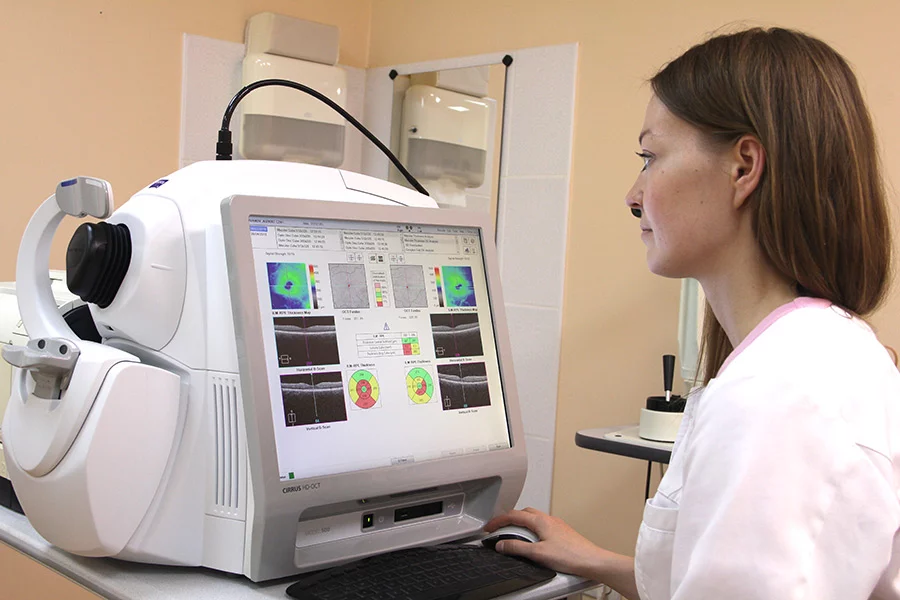

Диагностика зрения: Когерентная томография сетчатки